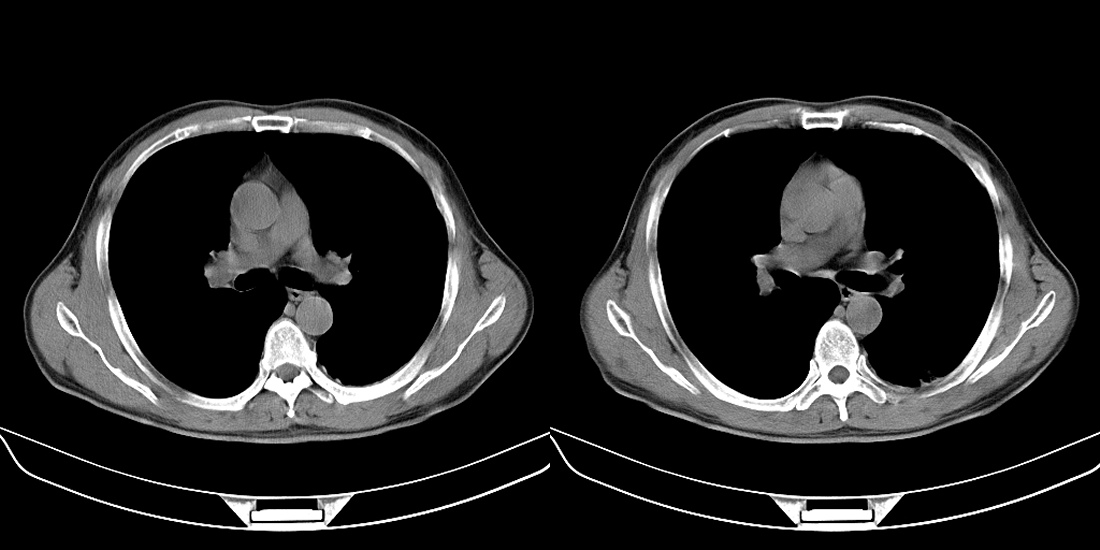

标题: CT10251:男性56岁,结核球? [打印本页]

标题: CT10251:男性56岁,结核球?

56岁男性,低热、消瘦,曾x线诊断肺结核。

双肺结核伴左上肺结核球形成

两肺多形性病变,支持肺结核.

两肺多形性病变,且在结核好发部位。支持肺结核.